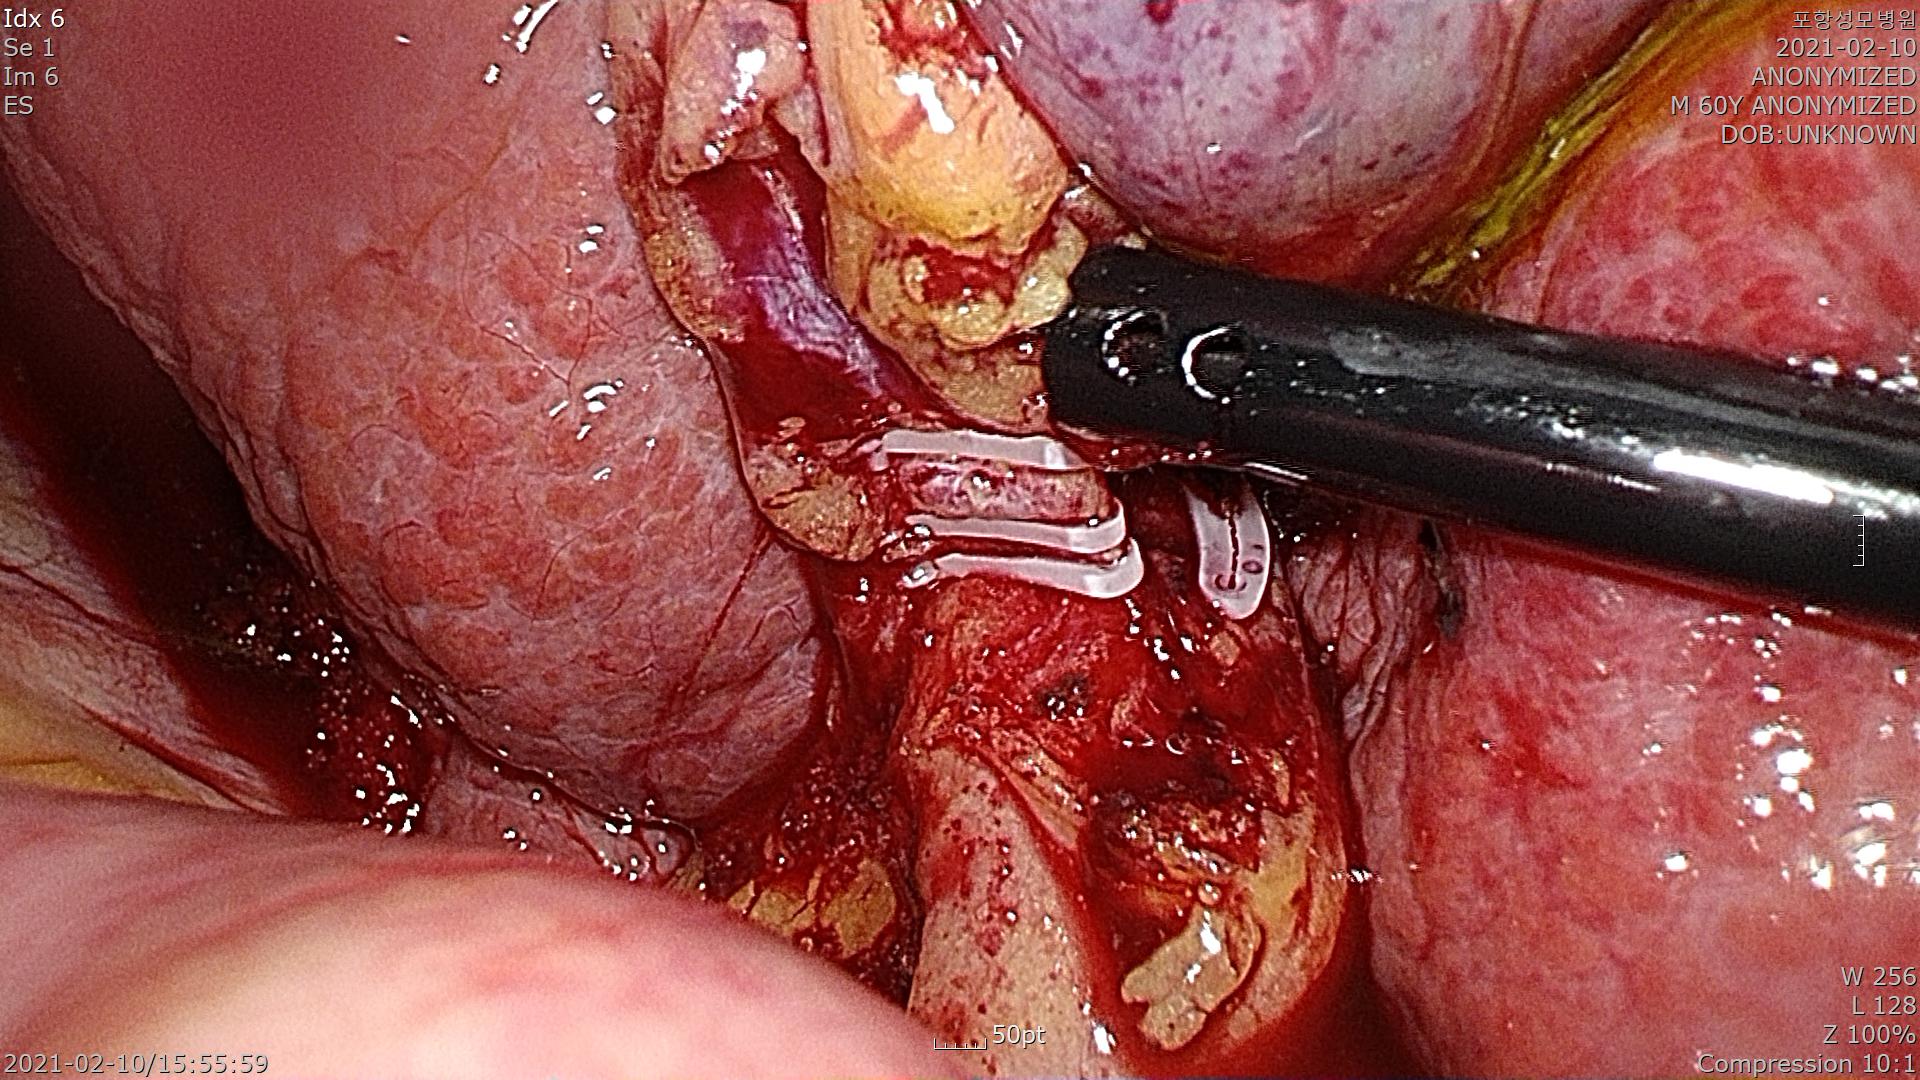

위 사진에서 보시듯이 간경화가 심해지면 원래의 매끈하고 붉은 간이 아닌 울퉁불퉁하고 딱딱한 간으로 변합니다.

간경화가 무척이나 심합니다.

담낭관을 확인하고 박리합니다.

담낭관을 결찰합니다.

간후벽에서 담낭을 분리합니다.

다행히 담낭이 잘 제거되었습니다.

간경화가 심했지만 수술은 20분 걸렸습니다.

담낭안에 담석이 없는 무결석 담낭염으로 확인되었습니다.